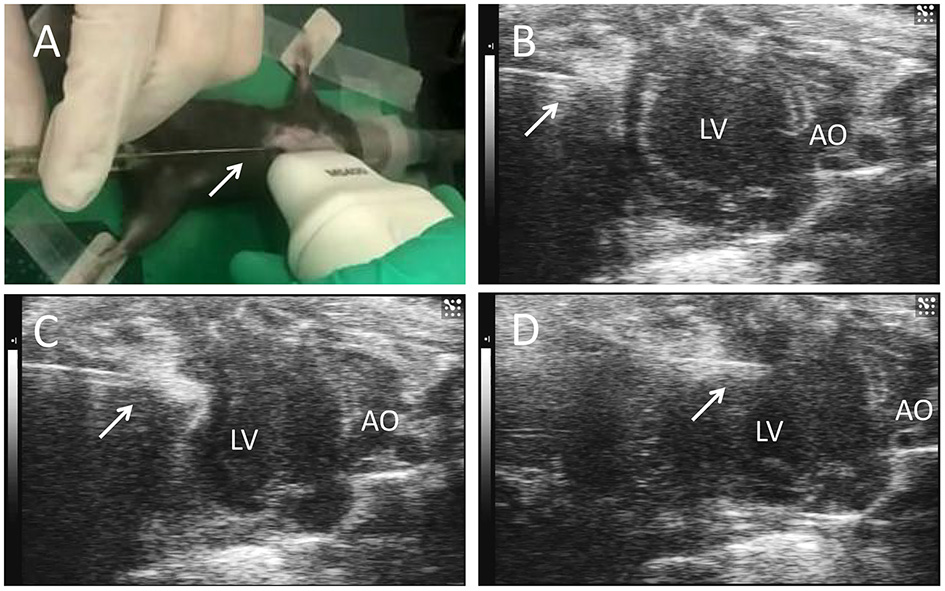

C57BL/6 mice induced MI by surgery. Feed 12-week-old mice at a temperature of 25°C and a humidity of 40–60% in a 12-h light/12-h dark cycle. Mice were anesthetized and maintained via isoflurane (1.5–2%) inhalation. After intubating and ventilating the mouse, perform thoracotomy in the third and fourth intercostal space on the left side of the mouse, and then ligate the left anterior descending coronary artery (LAD) with 8-0 non-absorbable sutures, and then close the chest muscles and skin. Then the surgical mice were randomly divided into three groups: single-dose cell therapy (SD) group and multiple-dose cell therapy (MD) group and MI-only group. The hiPSC-CM suspension (3 × 105 cells in 10 μl) was percutaneously injected into 3 LV infarcted border intramyocardial sites (1 × 105 cells per inject site) with a microsyringe (Cat. 84250; Hamilton Company) guided by a resolution micro-ultrasound system (Vevo 2100; Visualsonics) through the long-axis view (SD groups, Figure 1); the equivalent volume of PBS was injected in the same way (MI-only group). Except for coronary artery ligation, mice in the sham operation group received all the surgical operations required for MI treatment. After injection, mice were injected intraperitoneally with buprenorphine (0.1 mg/kg) every 12 h for 3 days, and carprofen (5 mg/kg) was injected intraperitoneally every 12 h for 12 days. To prevent graft rejection, we administered cyclosporine A (10 mg/kg/day) from 2 days before the injection of hiPSC-CMs until the mice were dissected. In addition to the first delivery, the MD group received repeated delivery of the same volume and concentration of hiPSC-CMs (3 × 105 cells in 10 μl totally, and 1 × 105 cells per inject site) at post-MI weeks 1 and 2 (MD groups, Figure 1). It is worth noting that the needle of the microsyringe was inserted below the xiphoid process of the sternum and entered the pericardial cavity along the upper margin of liver to avoid injury to the liver or lung (Supplementary Figure 2).

Figure 1

Echocardiography-guided percutaneous left ventricular intramyocardial injection. Mice were anesthetized and maintained via isoflurane (1.5−2%) inhalation. After depilation locally, and guided by transthoracic echocardiography, the needle (arrows) of a microsyringe was inserted below the xiphoid process (A) and along the upper margin of the liver (B), entered the pericardial cavity (C), and finally was injected into the anterior wall of the left ventricle (D) to deliver the cells. LV, left ventricle; AO, ascending aorta.